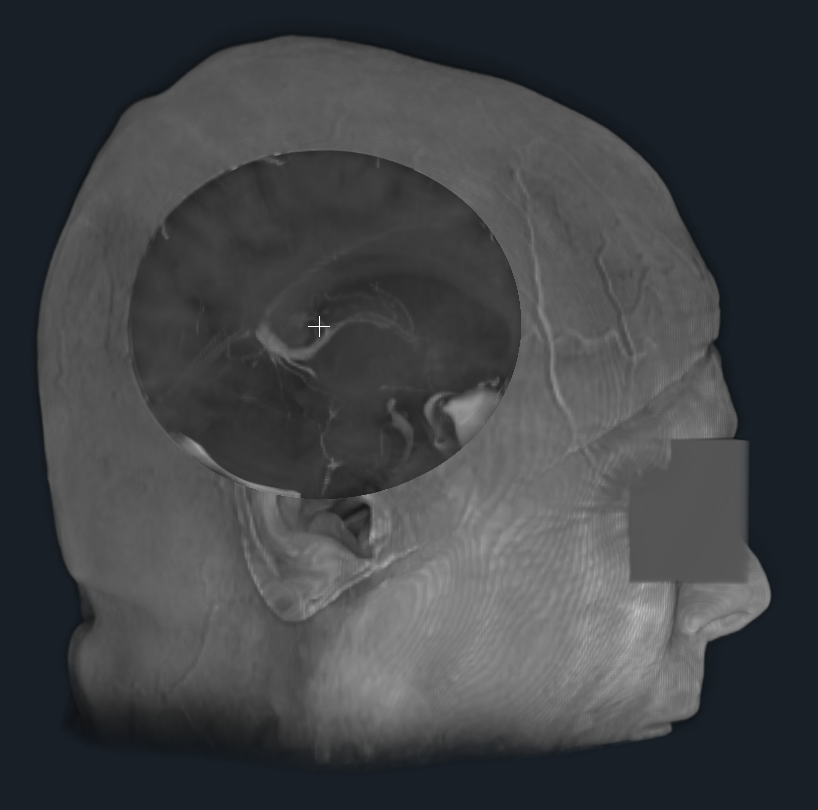

- Provided a proof of concept (python script) for dynamic shader editing in Slicer (see image, video and link to script below)

Proof of concept

Result

Illustrations

| Philips 3D US | Chroma-depth in PRISM | Depth peeling in PRISM |

|---|---|---|

|

|

|

| Edge enhancement in PRISM | Decluttering in PRISM | Volume carving in PRISM |

|---|---|---|

|

|

|

| Blood flow animation in PRISM | ||

|---|---|---|

|